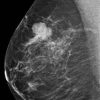

Ung thư vú

» Thông tin: Nữ giới – 55 tuổi.

» Lâm sàng: Khối tuyến vú.